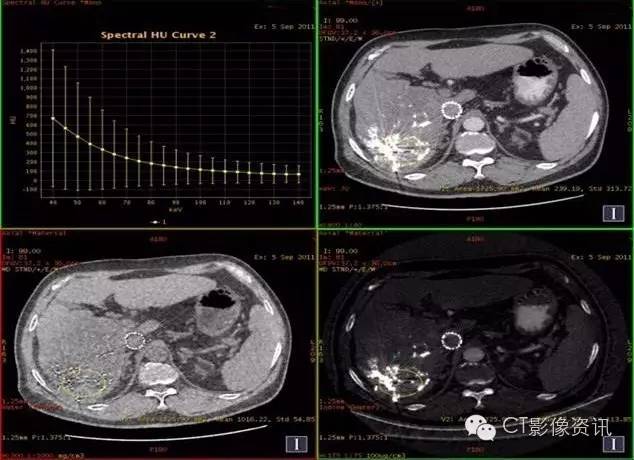

病史资料 男性,56岁,肝癌栓塞术后复查。

扫描参数 模式:GSI-22 375mA@0.7sec/rot@DC40mm@SFOV Body Large 螺距:0.984:1 平扫+增强扫描

动脉期:碘8.56,水1016.22

结论:此例平扫、增强多期碘基物质定量无显著差异。栓塞治疗效果较好。

临床优势 肝癌栓塞后,因碘油和术后炎性反应的影响,短期内难以评估手术效果。通过能谱成像GSI分析,比较增强后碘含量与平扫时碘含量(有时可用水含量)的变化及变化趋势,来判断肝癌病灶是否还有强化,评估栓塞治疗的疗效和预后,并可指导临床进一步治疗。